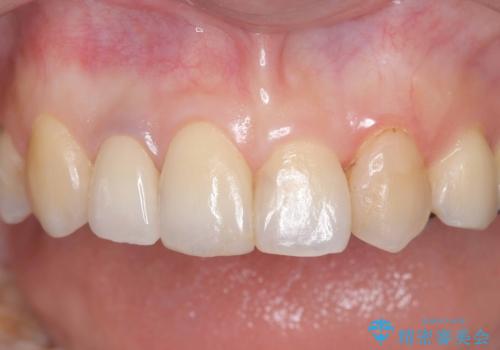

セラミック治療 → 前歯クラウン(オールセラミック)

前歯の見た目を良くしたい オールセラミッククラウン

金属色の見える前歯 オールセラミックで審美治療